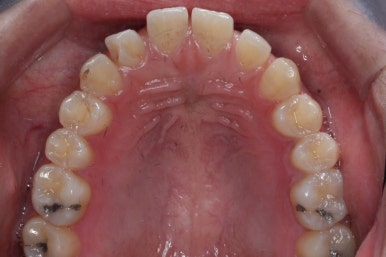

위 사진은 부산치아교정치과에 내원하셨을 대 당시의 입안 모습입니다.

치아들 사이에 전반적으로 틈이 많이 있는 상태입니다.

앞니 사이의 틈을 제일 보기 싫어하실 것 같으므로 앞니 부터 빠르게 틈을 보아줍니다. 대신 작은 어금니 부위로 틈을 모으는 작업을 하게 됩니다.

이번 환자분의 경우 부산치아교정치과에서는 그 원인을 "혀"로 봤습니다.

혀는 말랑말랑하지만 잘못된 혀의 위치(혀내밀기 등)가 지속될 경우 치아를 뻐드러지게 하거나 앞니를 밀어내며 치아 사이의 틈을 만들어낼 수 있습니다. 성장기에는 골격의 성장을 잘못된 방향으로 만들기도 합니다. 교정치료에서 매우매우 중요한 것이 바로 "혀" 입니다.

틈을 쭉 모으다 보면 앞니 치아들이 전반적으로 뒤로 들어가게 되고 혀위치를 침범하게 됩니다. 혀가 다시 내미는 동작을 했을 때, 치아 사이 틈이 다시 발생하게 될 우려가 매우 크게 됩니다.

따라서 이번 환자분의 경우는 앞니를 앞으로 혹은 뒤로 위치변화를 주지 않고 앞-두의 위치는 처음 그대로 유지시키고자 이런 방법을 택했습니다.

바로 미니스크류 입니다. 위 사진에서 화살표 부분이 바로 미니스크류 입니다.

뼈에 단단히 고정해 놓고 어금니를 앞으로 당겨오는데 사용을 하게 됩니다. 교정치료 후에는 제거하게 되며 긍방 뼈가 차기 때문에 별로 걱정은 하지 않으셔도 됩니다.